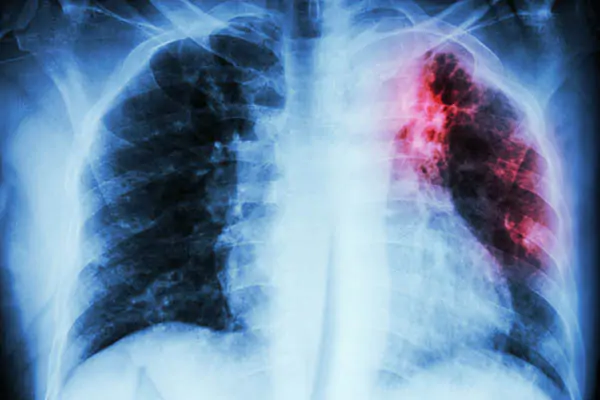

Chụp X-quang ngực: Loại trừ các nguyên nhân khác gây triệu chứng tương tự.